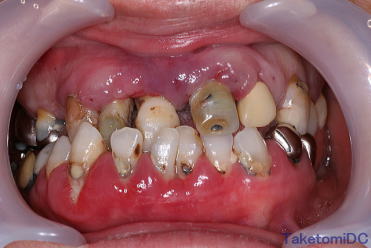

虫歯+不正咬合+歯槽膿漏の症例

虫歯と不正咬合と歯槽膿漏で悩まれていた患者さんの症例です。

下の歯を少し矯正しましたが後はすべて保険診療内で治しています。

矯正費用が10万円くらいかかりましたが全部で15万円くらいでここまで治っています。まだ歯槽膿漏の治療や小さな虫歯の治療は残っていますが見違えるほど綺麗になっています。

もちろん同じ方の写真ですよ! |